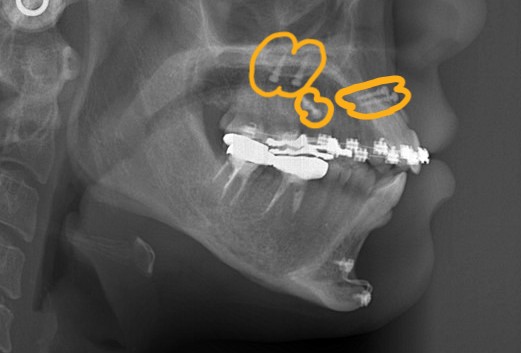

矯正後の状態をレントゲン写真で確認すると、

術前も口元にEラインを引くことが出来ました(レントゲン参照)が、お顔全体のバランスという意味で、同じEラインであっても術前と術後ではスッキリ感が異なります。

ただ、せっかくアンカースクリューを植立したので、臼歯部の圧下だけでも行い、下顎の反時計回りの回転によるオトガイ部の前方移動(→ Eラインを引くうえで有利になる)と、前歯部の開口傾向の改善だけは図ることにしました。 この作戦だと時間を短縮できます。